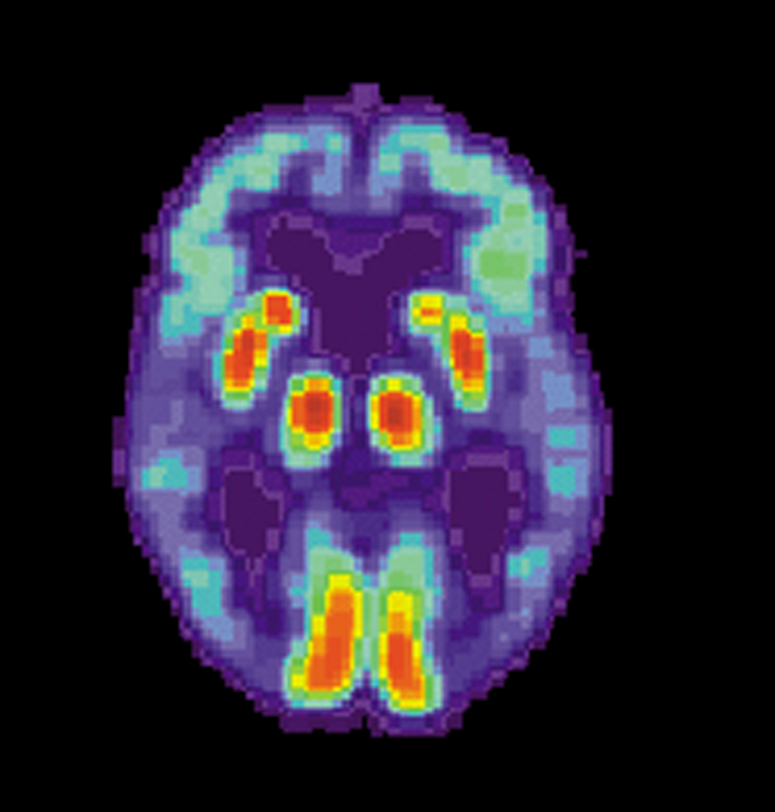

US National Institute on Aging image In this image from the US National Institute on Aging, Alzheimer’s Disease Education and Referral Center, a PET scan of a human brain with Alzheimer’s disease. The scan indicates a loss of function in the temporal lobe.

(THE CONVERSATION) — Alzheimer’s disease is the most common cause of dementia. It slowly destroys memory, thinking and behaviors, and eventually the ability to carry out daily tasks.